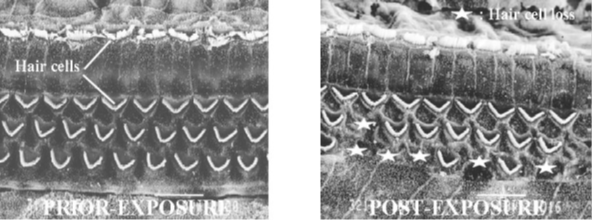

Sensorineural hearing loss tends to be a permanent condition that is often associated with irreversible damage to the inner ear. The normal aging process and excessive noise exposure are both notable causes of sensorineural hearing loss. Studies show that exposure to noise damages the sensory cilia that line the cochlea. Even moderate noise can cause twisting and swelling of the cilia and biochemical changes that reduce cilia sensitivity to mechanical motion, resulting in auditory fatigue. As the severity of the noise exposure increases or if the noise exposure is chronic, the cilia and supporting cells disintegrate and the associated nerve fibers eventually disappear. Occupational noise exposure is a significant cause of sensorineural hearing loss, which appears on sequential audiograms as declining sensitivity to sound, typically first at high frequencies (4,000 Hz), and then lower frequencies as damage continues. Often the audiogram of a person with sensorineural hearing loss will show a "Notch" between 3,000 Hz and 6,000 Hz, and most commonly at 4,000 Hz. This is a dip in the person's hearing level at 4,000 Hz and is an early indicator of sensorineural hearing loss due to noise. Results are the same for audiometric hearing tests and bone conduction testing. Sensorineural hearing loss can also result from other causes, such as viruses (e.g., mumps), congenital defects, and some medications. Modern hearing aids, though expensive, are able to adjust background sounds, changing signal-to-noise ratios, and support hearing and speech discrimination despite the diffuse nature of sensorineural hearing loss. The role of cochlear implants remains unclear.